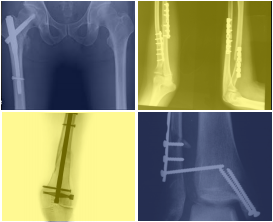

Por primera vez el Centro Médico Teknon – Grupo Quirónsalud acoge el I Curso de Osteosíntesis "Actualización del tratamiento quirúrgico de las fracturas" el viernes, 1 de abril, con la participación de destacados especialistas en traumatología de los hospitales del Grupo Quirónsalud en Catalunya para intercambiar experiencias y departir sobre los últimos avances en Cirugía Ortopédica y Traumatología. En este curso de osteosíntesis o tratamiento quirúrgico de las fracturas óseas se abordarán tanto las técnicas de implantología traumatológica como de Traumatología Mínimamente Invasiva, consistentes en la práctica de nuevas vías de acceso que disminuyen el riesgo de complicaciones postquirúrgicas y acortan el tiempo de recuperación tras la cirugía.

"La osteosíntesis de las fracturas óseas es un área muy específica de la especialidad de la Cirugía Ortopédica y Traumatología, en constante evolución debido al continuo desarrollo de nuevos materiales y vías de abordaje para colocarlos. Antiguamente, el objetivo del tratamiento de las fracturas era la cicatrización o consolidación ósea, pero hoy en día este objetivo es insuficiente. La dinámica de la sociedad actual exige que la consolidación del hueso se realice en el menor tiempo posible y en ausencia de complicaciones", explica el Dr. David Roca, cirujano ortopédico y traumatólogo del Centro Médico Teknon y director del curso.